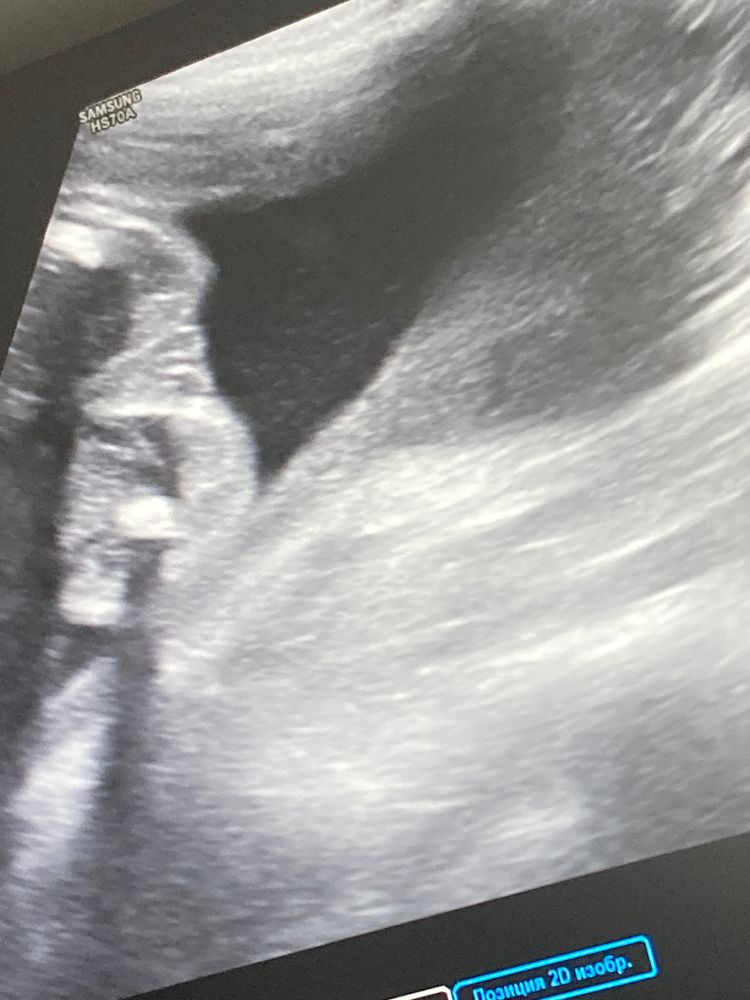

Amina Aliyeva в Зачатие 2 года УЗИ пол Ребенка второй скрин Фолликулометрия здравствуйте кто на фото мальчик или девочка ? 23нед Посмотрите еще 20 записей на эту тему Лучший ответ Виктория Смирнова Ну если я правильно смотрю, то там кофейное зернышко, значит девочка) 27.01.2024 Ответить Отменить Ответить Ирина Лапина На девочку похоже. 27.01.2024 Ответить Мама Лиля Я вижу девочку. 27.01.2024 Ответить Lolova Девочка 27.01.2024 Ответить Кто то с форума Похоже на девочку) 27.01.2024 Ответить Ель Богатырь 27.01.2024 Ответить Amina Aliyeva Комментарий удален 27.01.2024 Ответить Светик Девочка 🍑 27.01.2024 Ответить Анна А вам на узи не сказали? Девочка 27.01.2024 Ответить Amina Aliyeva Анна, сказали просто немного сомневаюсь 27.01.2024 Ответить Анна Amina Aliyeva, тут же прям очевидно)) 27.01.2024 Ответить Amina Aliyeva Анна, 🙏😇 27.01.2024 Ответить Анна Amina Aliyeva, поздравляю вас с принцессой 😊 27.01.2024 Ответить Amina Aliyeva Анна, спасибо 😇это уже третья😁 27.01.2024 Ответить Валерия Amina Aliyeva, у меня 4 девочки и 5й сыночек,сейчас 6го планируем) 27.01.2024 Ответить Анна Amina Aliyeva, папа ювелир 😅 27.01.2024 Ответить Плодное яйцо Скудные месячные и плохой кровоток связаны ? Чаты Беременных Выберите чат: Январята-2026 Февралята-2026 Мартята-2026 Апрелята-2026 Майчата-2026 Июнята-2026 Июлята-2026 Августята-2026